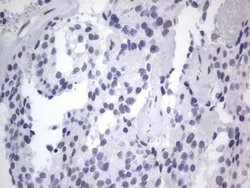

RBFOX1 Mouse anti-Human, Clone: OTI4F9, lyophilized, TrueMAB™

| Immunohistochemistry (Paraffin), Western Blot | |